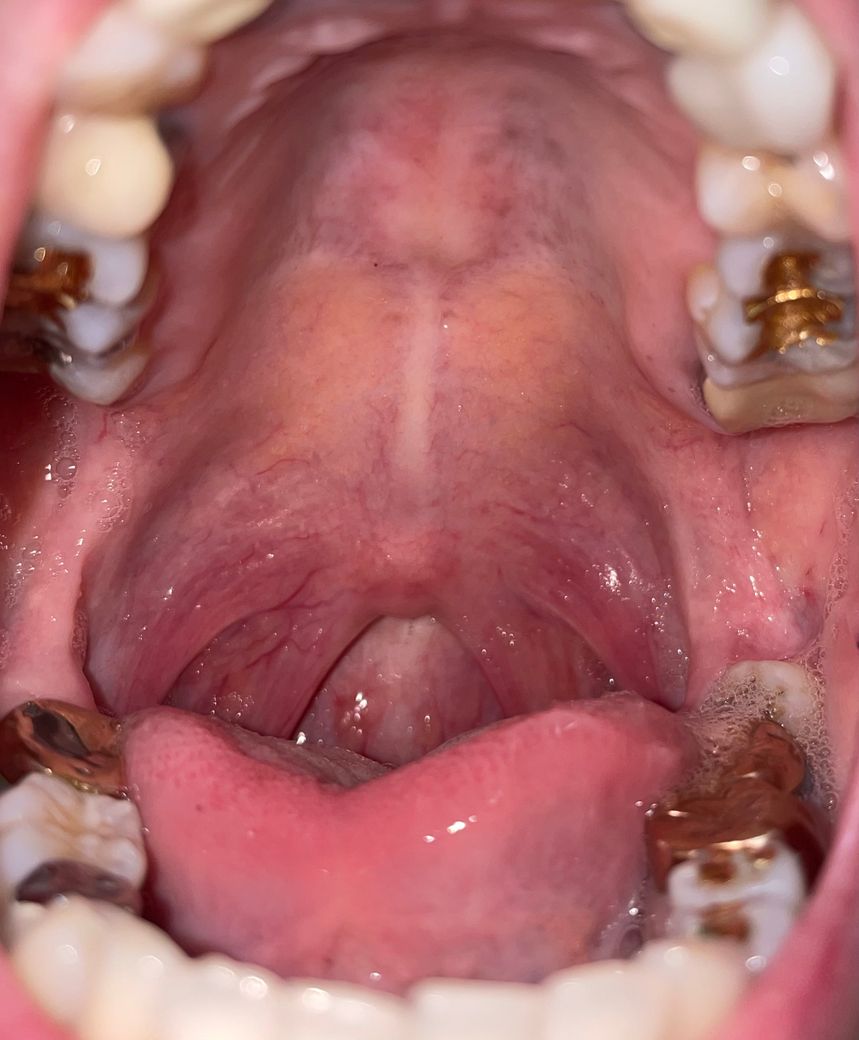

가만히 있을때는 괜찮은데 입맛을 다시거나 입안을 움직일때 입천장 쪽이 당기는듯한 느낌이 있어요

사진상으로 보여지는 문제(붓기라던지)가 있을까요?

올리신 사진의 소견을 보았을 때에는 딱히 언급하신 증상을 유발할만한 소견이 있어 보이지 않으며, 이외에 기타 문제가 있다고 판단을 내릴 만한 이상 소견이 크게 있어 보이거나 하지 않습니다. 사진의 소견만 놓고 보았을 때에는 딱히 크게 문제가 있을 것으로 사료되거나 하지는 않아 보입니다.

보여주신 사진에선 목젖과 편도 부분이 약간 붉어보이고 입천장은 약간 보라색빛? 처럼 보이는게 다에요. 붓기는 사진이 입체적이지 않아서 확인이 안됩니다

말씀하신 증상 관련 답변 드리자면 여러 가지 원인이 있을 수 있습니다. 가장 흔한 원인은 구강 점막의 건조나 입안의 자극입니다. 또한 구내염, 입천장의 염증, 또는 근육의 긴장이 원인일 수 있구요. 입을 자주 움직일 때 당기는 느낌이 있다면, 근육이나 점막에 작은 자극이 있을 가능성도 있어요. 만약 통증이 동반되거나 증상이 지속된다면, 구강 내과나 치과에서 검사를 받는 것이 좋습니다